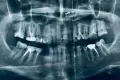

Если при просмотре рентген-снимка пломбировка канала смотрится как нормальная, изменений на верхушке корня нет, то перепломбировывать не надо. Любое вмешательство увеличивает риски, проще говоря, можно сделать хуже.

Другая ситуация, если на снимке выявлены пустоты, не до конца запломбированные каналы, есть разрежения, изменения на верхушке корня, либо зуб ранее побаливал при надавливании, накусывании, слегда поднывал, например при изменении погоды и т.д. В таких случаях лучше зуб перелечить, чтобы избежать проблем с будущей коронкой.